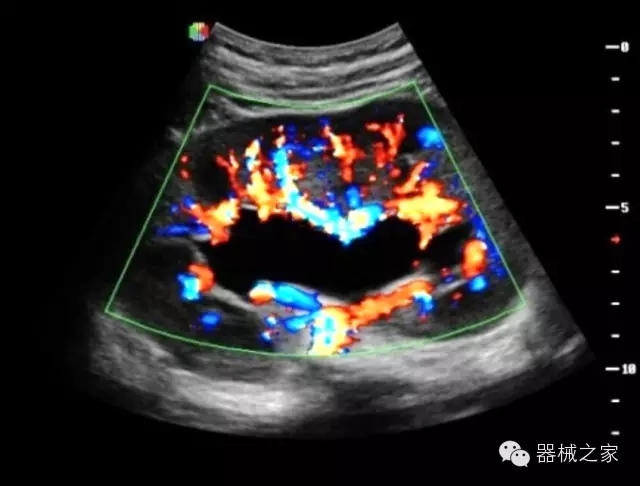

臨床圖片賞析

產(chǎn)品特點

優(yōu)異的成像技術(shù)

·智能微血流成像技術(shù):智能微血流捕捉技術(shù)可以提取出隱藏在背景噪聲中的弱血流信號,大大提高低速血流的敏感性;